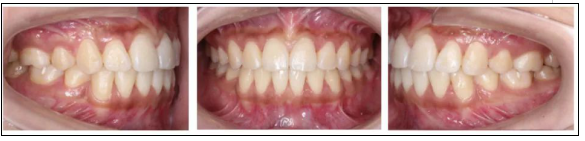

2.* 口內(nèi)檢查(以及調(diào)節(jié)前后口內(nèi)對比):

* 口內(nèi)檢查(以及調(diào)節(jié)前后口內(nèi)對比):

矯正前

口腔衛(wèi)生稍差,軟垢色素(+),牙齦略充血、腫大;恒牙列;左側(cè)磨牙遠中關(guān)系,右側(cè)磨牙中性關(guān)系;前牙開牙合、深覆牙合;上下牙弓尖圓型;上下牙列輕度擁擠;上中線基本正,下中線左偏。

矯正后

上下牙列齊,前牙覆牙合覆蓋正常,中線正,雙側(cè)尖牙及磨牙關(guān)系中性,雙側(cè)后牙尖窩關(guān)系良好。